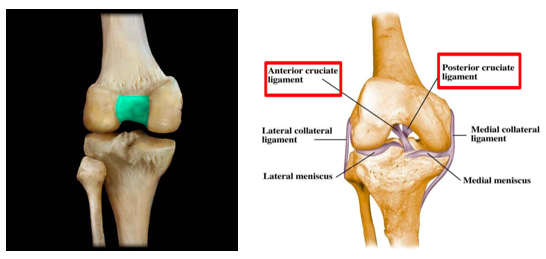

Describe the structure and function of the intercondylar fossa in the distal femur

Where do the posterior and anterior cruciate ligaments of the knee attach to on the distal femur?

- Facet for attachment of anterior cruciate ligament – found on the lateral wall of the intercondylar fossa (smaller)